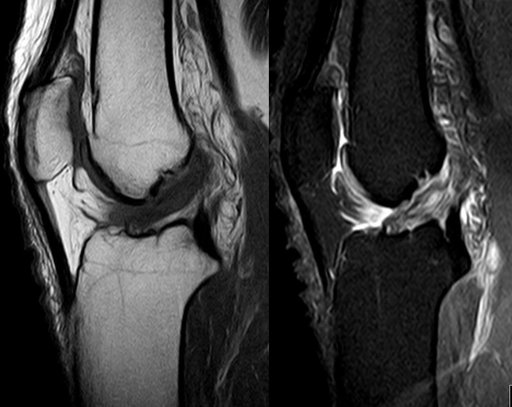

Complete ACL disruption, lateral bone bruising (pivot-shift), medial meniscus complex tear